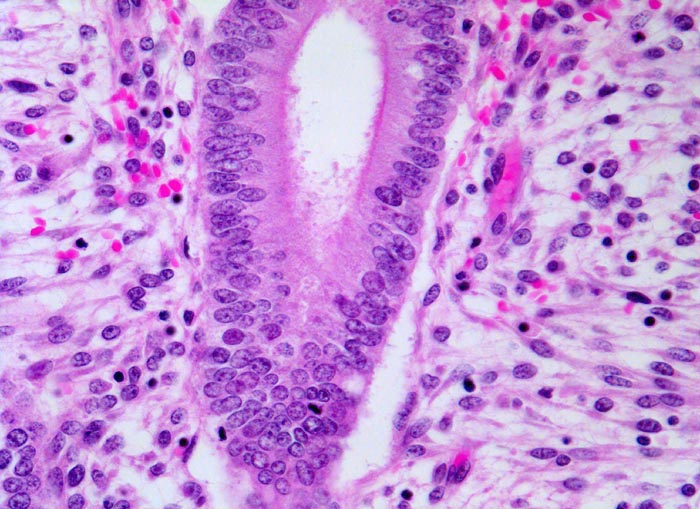

• Hyperplasie mit Atypie (AH)/Endometrioide intraepitheliale Neoplasie (EIN) Die hyperplastische Mukosa ist verdickt (2-3cm statt normal 0.2-1.2cm), homogen-weisslich glasig und weich. Die Drüsen sind verstärkt verzweigt, zystisch transformiert und ausgekleidet von mehrreihigem Epithel. Bei der Hyperplasie beträgt das Drüsen-Stroma Flächenverhältnis >1:1. Die Vorstufe der Hyperplasie mit gleichartigen architektonischen Veränderungen aber einem Drüsen-Stromaverhältnis <1:1 bezeichnet man als unregelmässig proliferiertes Endometrium. 1-3% der Frauen mit einer Hyperplasie des Endometriums ohne Atypie entwickeln im Verlauf ein gut differenziertes endometrioides Adenokarzinom. Das Risiko für die Entwicklung eines endometrioiden Adenokarzinoms ist dagegen viel höher bei Vorliegen einer Hyperplasie mit Atypie (> 1074) (> 1075) oder einer endometrioiden intraepithelialen Neoplasie (=Präneoplasie) (> 10369). Bei einem Viertel bis einem Drittel der Patientinnen mit solchen Läsionen in der Kurettage wird in der nachfolgenden Hysterektomie oder innerhalb eines Jahres die Diagnose eines endometroiden Adenokarzinoms gestellt. Das Karzinomrisiko ist 14x erhöht bei der atypischen Hyperplasie bis 45x bei der EIN. In Einzelfällen kann die Abgrenzung einer atypischen Hyperplasie oder einer EIN von einem Karzinom am Kurettagematerial sehr schwierig sein. Beim invasiven Karzinom sind die Drüsenarchitekturstörungen ausgeprägter und zwischen den Karzinomdrüsen fehlt das Stroma stellenweise vollständig.

• Proliferierendes ein- oder mehrreihiges Epithel mit länglichen hellen Kernen und Mitosen.

• Einige Drüsen werden von metaplastischem tubarem Epithel oder Flimmerepithel ausgekleidet. Das sollte der Kliniker dem Pathologen mitteilen: